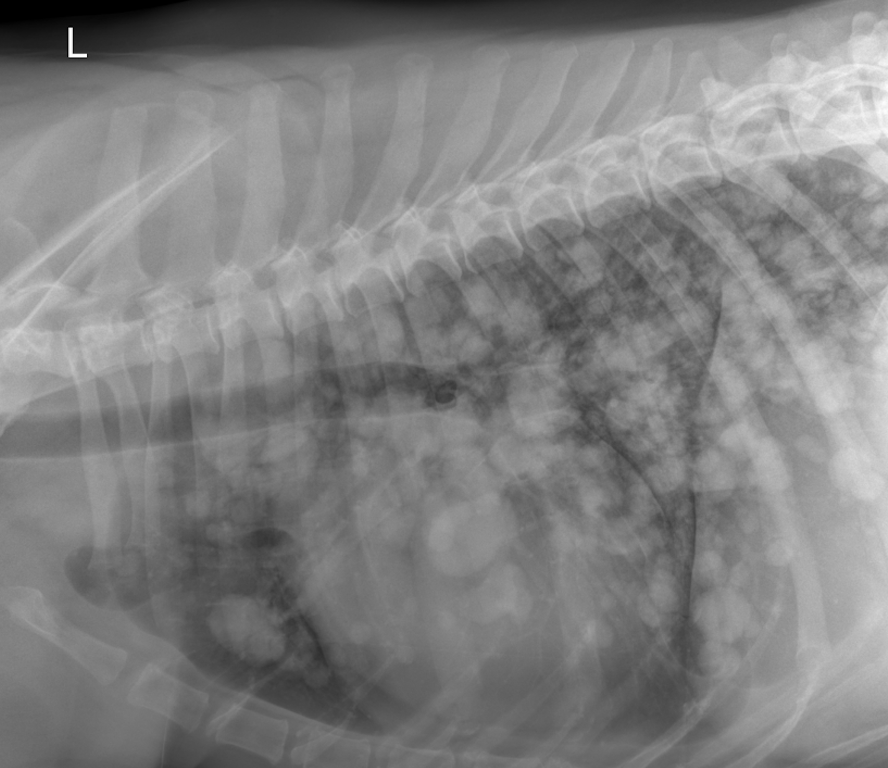

Im Thoraxröntgen zeigen sich in allen Lungenlappen multifokale, noduläre Weichteilverschattungen unterschiedlicher Größe, wobei die größte eine Länge von 3,8cm und eine Breite von 2,6cm aufweist (exemplarisch pinke Pfeile). Generalisiert besteht zudem vor allem in den kaudalen Lungenlappen geringgradige (pink gestrichelter Pfeil), sowie im akzessorischen Lungenlappen moderate unstrukturierte Lungenzeichnung. Die Herzsilhouhette ist generalisiert globoid vergrößert (pink gestrichelte Linien). Die kranialen Lungengefäße wirken prominent, sind jedoch kleiner als die proximale Breite im Bereich der vierten Rippe (pinke Pfeilköpfe). Mediastinale Strukturen, Pleuralraum, Trachea, Ösophagus, sowie sichtbare ossäre Anteile stellen sich ohne besonderen Befund dar.

Das globoide Herz kann auf einen Perikarderguss hinweisen, jedoch kann eine Kardiomegalie anderer Genese gepaart mit einer Aufnahme in Diastole nicht ausgeschlossen werden.